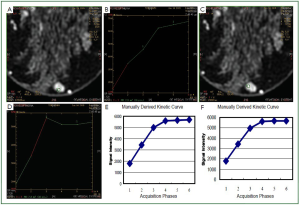

We observed that in a number of cases of MRM lesions, there was a movement of the ROI in different phases of the dynamic study of a lesion, possibly due to respiratory motion artifacts (Figure 1). For example, at the third phase of the dynamic study the ROI was located in the center of the lesion, while in other phases (1rst, 5th, 6th) the ROI was found at the periphery of the lesion or even outside the lesion and vice versa.

Figure 1. Six images (A-F) representing the different phases of the dynamic image acquisition at the same position. In the third phase of the dynamic sequence (C), two ROIs (a large peripheral and a small central) were delineated. It is observed that by deriving the kinetic curves using the software of the system, apart from the lesion, a part of the surrounding tissue is included in the two ROIs in the phases A, E and F compared to phase C. Also, the distances of the large ROI from stable reference point (muscle and skin) that were measured in phase C, were not the same in the phases A, E, and F.